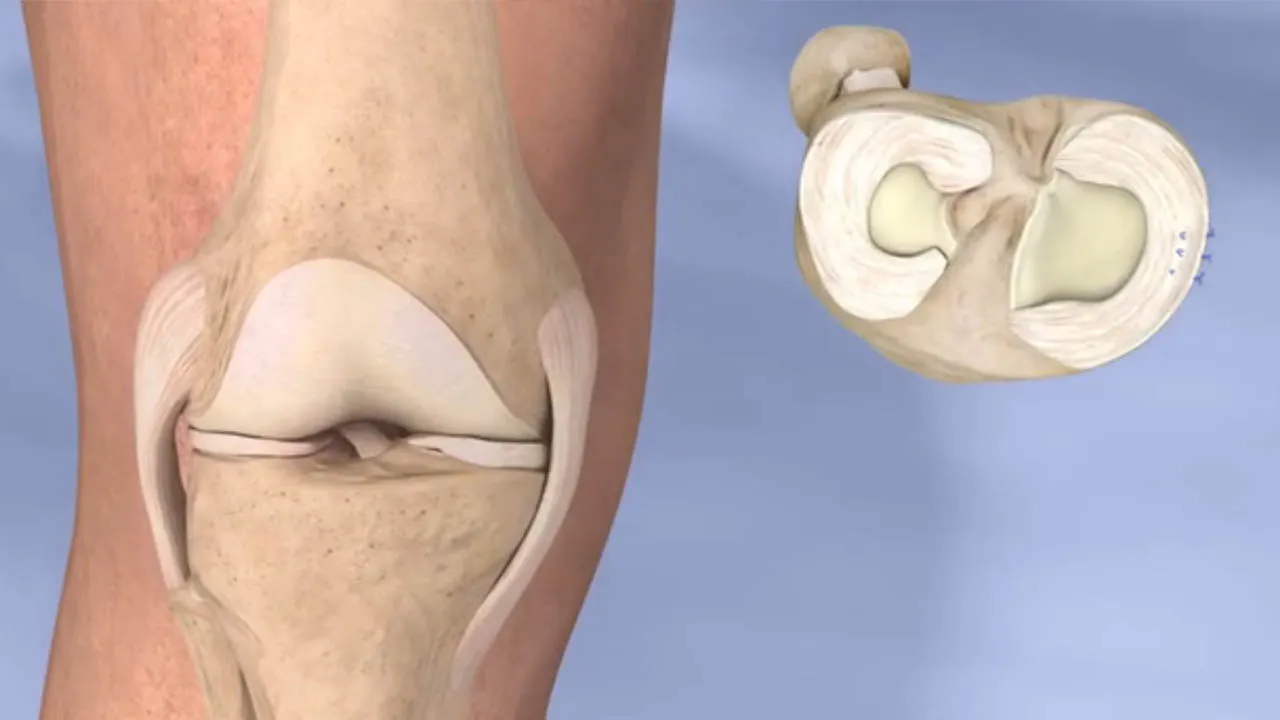

مینیسک چیست و چرا پاره میشود؟

مینیسک دو غضروف نیمهلالی شکل در داخل مفصل زانو است که بین استخوان ران و ساق قرار میگیرد. وظیفه اصلی آن جذب ضربه، افزایش ثبات زانو و جلوگیری از ساییدگی مفصل است. زمانی که زانو دچار چرخش ناگهانی، پیچخوردگی شدید یا فشار بیش از حد شود، مینیسک تحت کشش قرار گرفته و ممکن است دچار پارگی شود.